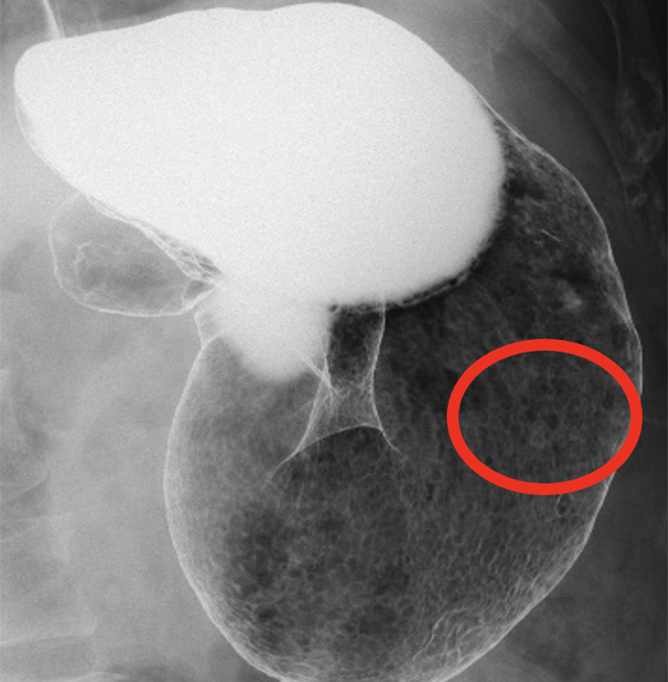

慢性期病院でありながら、最新鋭の64列CT装置・レントゲン装置(FPD)・X線TV装置・骨密度測定装置(DXA)などを取り揃えており、高い医療技術で皆様の診療の手助けをさせていただきます。